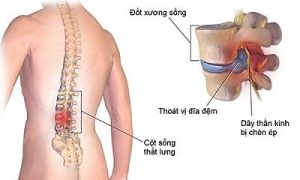

Những thói quen ăn uống giúp ‘đẩy lùi’ thoát vị đĩa đệm

Thoát vị đĩa đệm là một căn bệnh không trừ một ai, có thể xảy...

Liệu pháp điều trị thoát vị đĩa đệm cột sống thắt lưng từ gốc rễ

Có những liệu pháp điều trị tận gốc thoát vị đĩa đệm cột sống thắt...

Các phương pháp trị dứt điểm thoát vị đĩa đệm cột sống cổ

Khi thấy đau âm ỉ kéo dài vùng cổ gáy rất có thể bạn bạn...

Những nguyên nhân dẫn tới thoát vị đĩa đệm cực kì nguy hiểm

Căn bệnh thoát vị đĩa đệm càng ngày càng phổ biến gây ra những cơn...